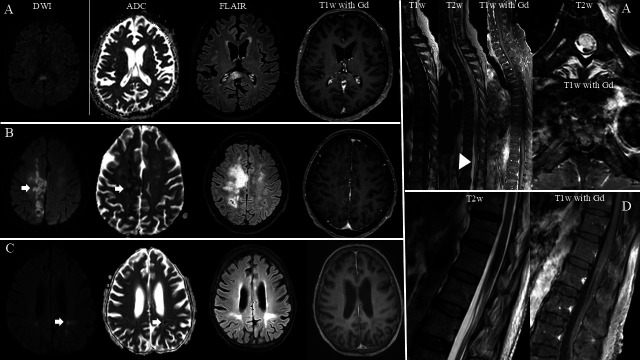

目的:本研究旨在阐明伴有神经系统受累的血管内大B细胞淋巴瘤(IVLBCL)患者的临床表现、实验室检查结果和转归,并对伴有和不伴有神经系统受累的IVLBCL进行鉴别。方法:2005年1月至2024年9月在泰国玛希隆大学Siriraj医院进行队列研究。分析临床资料、实验室值及中枢神经系统影像学结果。分类变量使用χ 2或Fisher精确检验进行比较,而连续变量则酌情使用Mann-Whitney U检验进行分析。结果:30例IVLBCL患者中,10例有神经系统受累,20例无神经系统症状,包括脊髓病(5例,50%);认知障碍(3例,30%);癫痫发作(2例,20%);视神经病变、偏瘫、同义性偏视、眩晕、全身性失语(各1例,占10%)。60%伴有神经系统受累的IVLBCL有全身性症状,包括持续发热、贫血、厌食和体重减轻。MRI表现为幕上、幕下及脊髓高强度病变,突出表现为纵向广泛的脊髓病变(4例,40.0%)。伴有神经系统受累的IVLBCL的中位生存时间为4.1个月(95% CI: 0.0 ~ 17.1个月),1年生存率为37.5%,2年生存率为25.0%。解释:本研究强调了伴有神经受累的IVLBCL的独特临床、实验室特征和影像学特征,并将其与无神经受累的IVLBCL进行了比较。尽管IVLBCL具有侵袭性,但早期识别这些发现对于准确诊断和改善患者预后至关重要。

Results: Of the 30 patients with IVLBCL, 10 had neurological involvement and 20 without neurological symptoms, including myelopathy (5 patients, 50%); cognitive impairment (3 patients, 30%); seizures (2 patients, 20%); optic neuropathy, hemiparesis, homonymous hemianopia, vertigo and global aphasia (each affecting 1 patient, 10%). 60% of IVLBCL with neurological involvement had systemic symptoms, including prolonged fever, anaemia, anorexia and weight loss. MRI showed hyperintense lesions in the supratentorial, infratentorial and spinal cord with the prominent findings being longitudinally extensive cord lesions (four patients, 40.0%). The median survival time of the IVLBCL with neurological involvement was 4.1 months (95% CI: 0.0 to 17.1 months), with a 1-year survival rate of 37.5% and a 2-year survival rate of 25.0%.